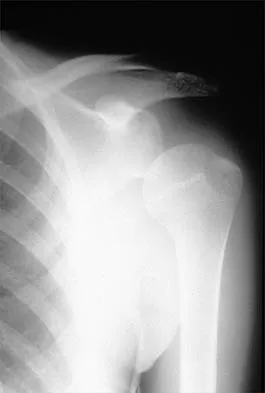

A 40-year-old woman who is an avid tennis player reports the insidious onset of progressive left shoulder pain for the past 2 months. Examination reveals full range of motion with a positive impingement sign. Strength in the supraspinatus and infraspinatus muscles is normal, although stress testing is painful. An earlier subacromial cortisone injection provided good, but only temporary relief. An AP radiograph of the left shoulder is shown in Figure 10. Management should now consist of

Explanation

The radiograph shows calcific deposits within the substance of the supraspinatus tendon. Patients with this condition are prone to recurrent bouts of acute inflammation in the shoulder. While the response to cortisone injection is often dramatic, repeated injections are not recommended because of injury to the collagen fibers. Good results have been obtained with arthroscopic evacuation of the calcium deposits. In one study, the addition of a subacromial decompression did not improve the results. Jerosch J, Strauss JM, Schmiel S: Arthroscopic treatment of calcific tendinitis of the shoulder. J Shoulder Elbow Surg 1998;7:30-37.